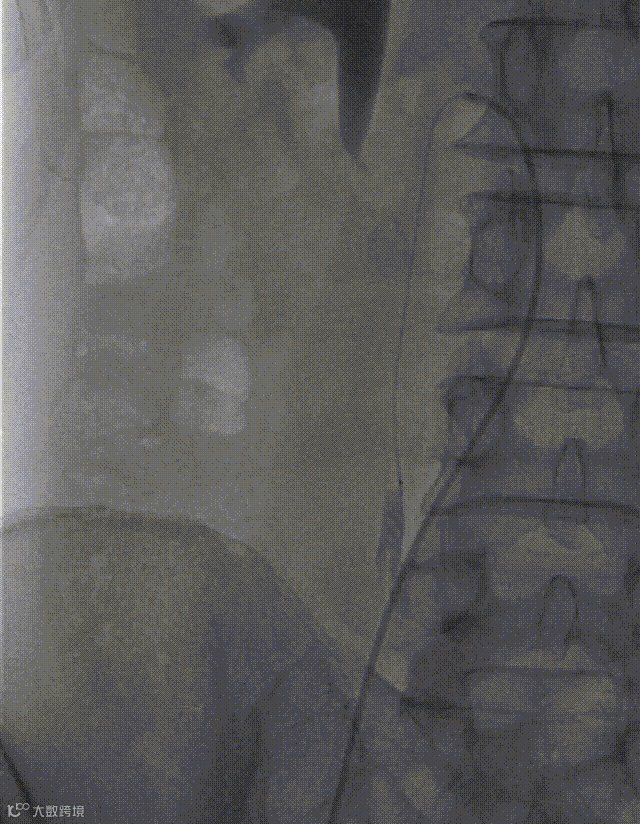

行股静脉穿刺置入6F短鞘,泥鳅导丝配合单弯导管顺利进入下腔静脉;

行高压造影显示:下腔静脉通畅,未见血栓、畸形;